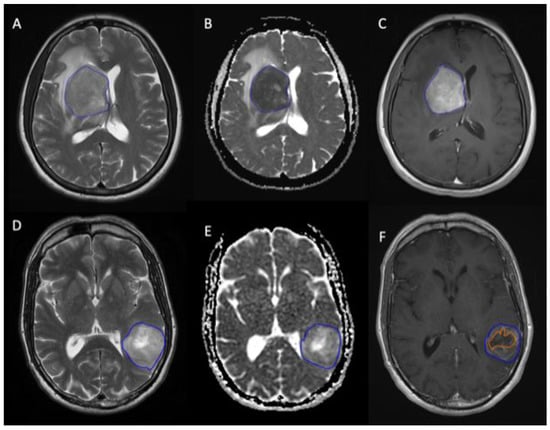

2.2. Tumour Segmentations

2.3. Texture Analysis (MRTA)